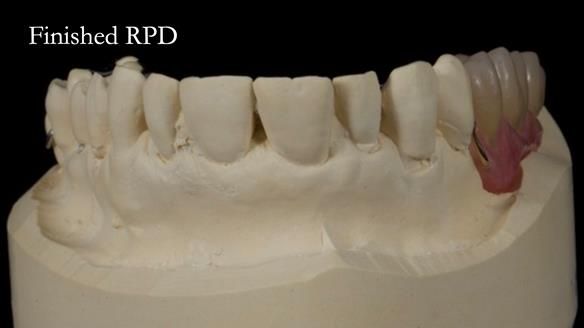

Welcome to Newsletter 64. I'll walk you through the process of providing a Mk 2 metal-based partial denture (RPD), for Ian a retired Veterinary Surgeon aged 78. The RPD was made at an increased vertical dimension and acted as an occlusal stabilisation splint - reducing the wear and bite force on the remaining natural teeth.